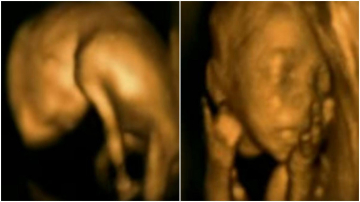

Imagini unice: cu ce se ocupă micuții în burticile mămicilor?